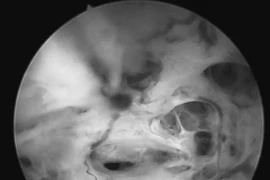

Anh N.V.Đ. (30 tuổi, trú tại xã Đèo Gia, tỉnh Bắc Ninh) nhập viện với tình trạng sưng nóng đỏ, chảy dịch mủ và loét vùng bao quy đầu. Kết quả thăm khám cho thấy có 3 viên bi dị vật nằm dưới da, vết khâu cũ nhiễm trùng nặng, hình thành giả mạc trắng. Ngay trong đêm, ê-kíp phẫu thuật đã tiến hành cắt bao quy đầu, lấy dị vật và làm sạch vùng tổn thương, tránh nguy cơ nhiễm trùng nặng thêm, lan rộng chuyển hoại tử.

Người bệnh được xử lý lấy bi ra thành công và đã được xuất viện. Ảnh Bệnh viện Đa khoa Bắc Ninh số 1